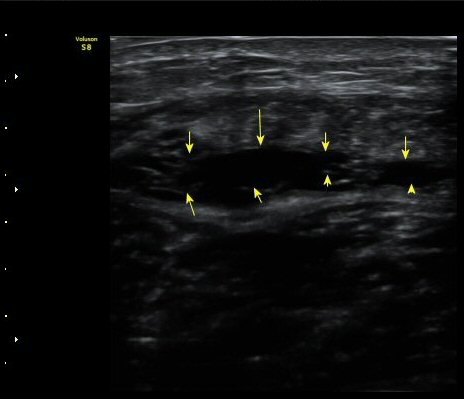

¼ö»ó ÈÄ 3ÁÖ Â°

1ÁÖ Àüº¸´Ù´Â ÀûÁö¸¸ ºñº¹±Ù°ú °¡Àڹ̱٠»çÀÌ¿¡ Ç÷¾×ÀÌ °í¿© ÀÖÀ½(±×¸² 8. 9)

ÃÊÀ½ÆÄ À¯µµÇÏ¿¡ Ç÷¾× ÈíÀÎ ÈÄ(µ¿¿µ»ó) Ç÷¾×ÀÌ ¸ðµÎ Á¦°Å µÈ(±×¸² 10) ÈÄ Åº·ÂºØ´ë·Î

¾Ð¹ÚÇÏ¿© µÎ ±ÙÀ°ÀÇ ¾ÐÂøÀ» À¯µµÇÔ.